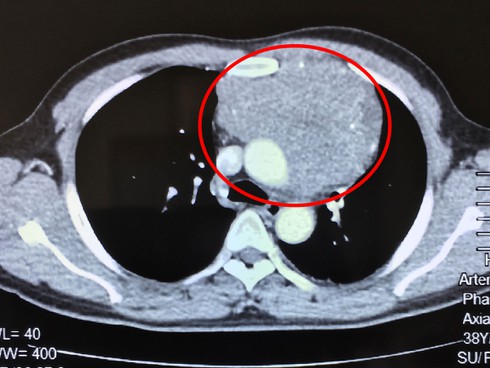

Hình ảnh khối u qua phim chụp |

Sau khi thăm khám kỹ lưỡng, thực hiện chụp CT Scan cùng các thăm dò cận lâm sàng cần thiết khác, các bác sĩ xác định có 1 khối u xuất phát từ trung thất trước (u ở phần lồng ngực giữa hai lá phổi), xâm lấn rộng vào màng ngoài tim, tĩnh mạch vô danh, thần kinh hoành bên trái, động mạch phổi và lan ra sau dính vào động mạch chủ ngực xuống.

Do khối u quá lớn, xâm lấn tim nên phải phẫu thuật gấp, ngày 16/6 ca mổ được tiến hành. Các bác sĩ đã tiến hành bóc tách khối u khỏi thần kinh hoành và các mạch máu quan trọng. Sau 2 giờ phẫu thuật, khối u rất lớn, khoảng 13x15x18cm (kích thước bằng quả tim của bệnh nhân) được lấy ra hoàn toàn.